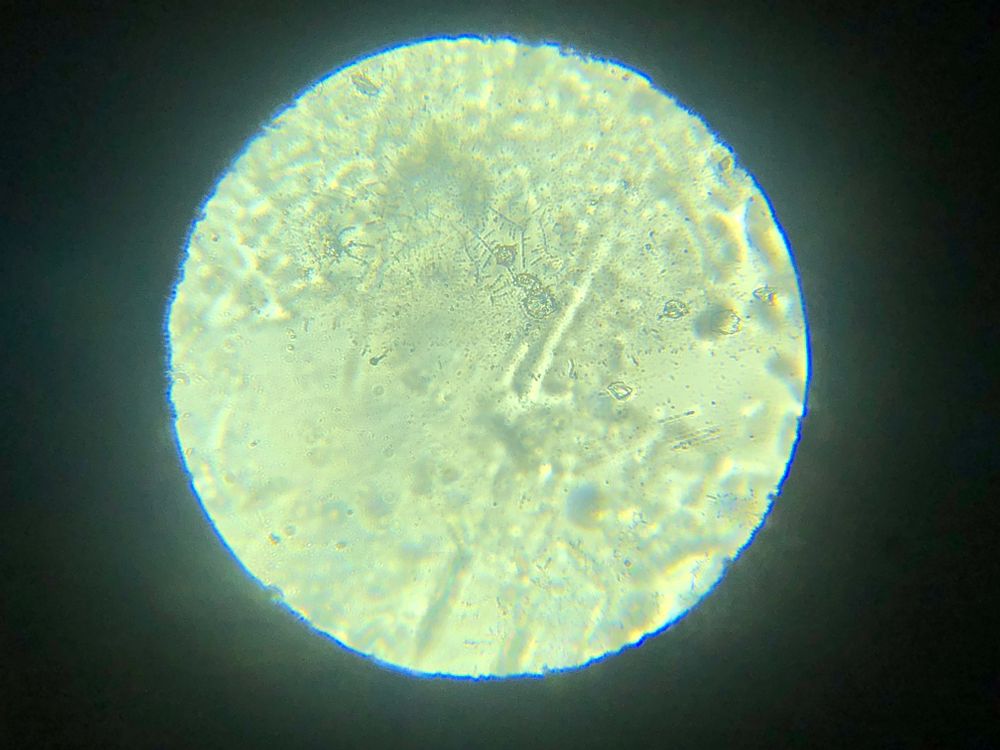

Я читала, что тесты на о показывают б. Возможно ли что и микроскоп на о, показал б.

Я уже ловила о в этом цикле, а по бт поймала из, ну как я думала, как тут вдруг. Вторая о или это первый признак б. Давайте попробуем разобраться. Подобного я р